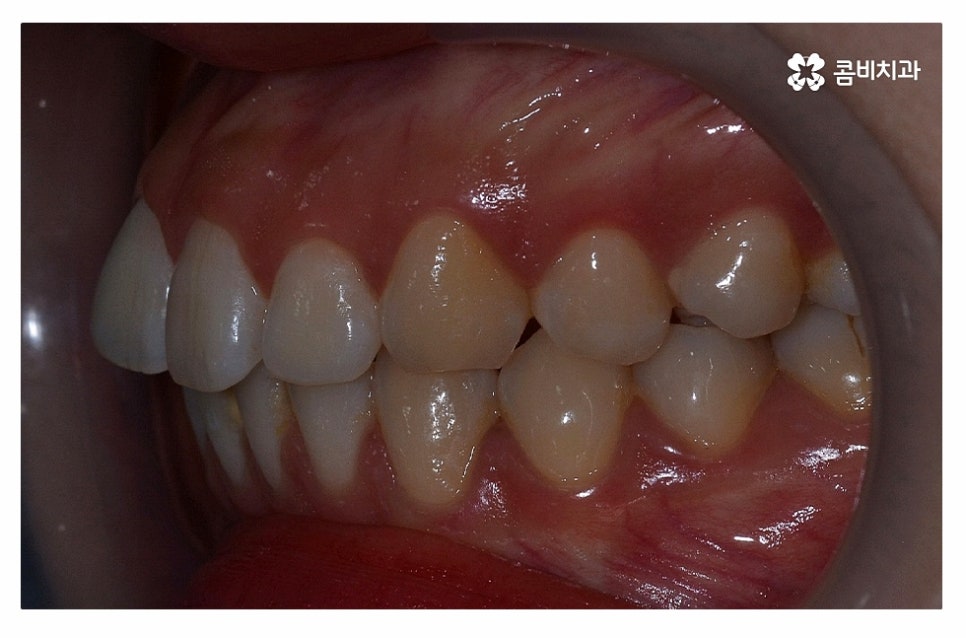

위 환자분의 경우 정면에서 보이는 치열은 가지런한 편이지만

치아가 돌출되어 돌출입으로 고민했던 사례이며

치아의 이동 공간 확보를 위해 발치 교정을 진행한 사례라고 할 수 있어요.

돌출입치아교정을 한다고 가정할 때 수술을 떠올리시는 분들도

많지만 비발치 혹은 발치를 통한 치아교정 만으로도

치료가 가능한 사례도 많기 때문에 정확한 진단이 중요하다고 할 수 있어요.